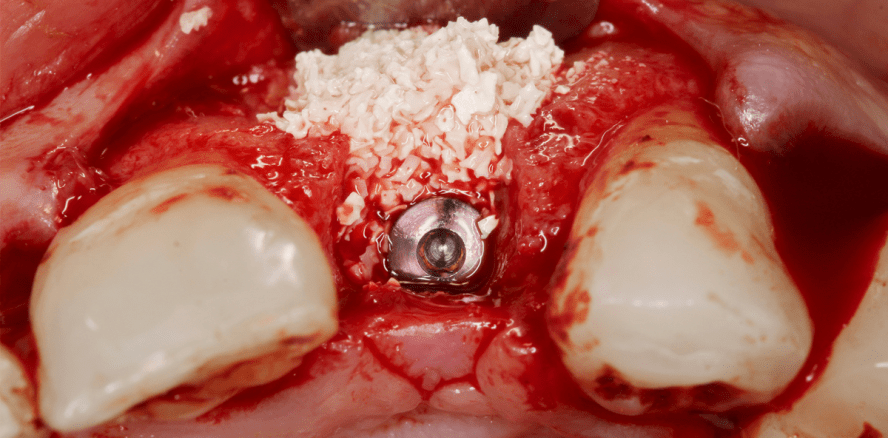

Foto: © josemagon – fotolia.com

Um Implantate im Kiefer zu verankern, ist oftmals ein vorheriger Knochenaufbau notwendig. Dieser wird mittels Knochenersatzmaterialien realisiert. Zwei Unternehmer aus Klagenfurt entwickeln momentan synthetisches Material, das die Knochenspenden von Mensch und Tier in Zukunft ersetzen soll.

Bei der Verwendung von natürlichem Knochenersatzmaterial kann es zu verschiedenen Problemen kommen: Die Eigenspende kann äußerst schmerzhaft sein, eine Fremdspende zu Abstoßungsreaktionen führen und der Einsatz tierischer Materialien ist aus religiösen Gründen manchmal nicht möglich. Die beiden österreichischen Unternehmer Horst Koinig und Werner Forstner tüfteln bereits seit drei Jahren an einer synthetischen Alternative zum natürlichen Knochenersatzmaterial.

Mit ihrem innovativen Material wollen sie die Prozedur aus Herstellung und Verankerung im Kiefer auf bis zu zwei Stunden verkürzen. Außerdem soll es mittels Bio-3-D-Druckverfahren optimal an den Kiefer des Patienten angepasst werden. Zusammen mit der Technischen Universität Graz wurde das Knochenersatzmaterial entwickelt und nun toxikologischen Tests unterzogen. Bis die österreichische Entwicklung auf den Markt kommt, braucht es laut den Unternehmern aber noch drei bis fünf Millionen Euro an Investitionen. Dass die sich lohnen, davon sind Koinig und Forstner fest überzeugt und tüfteln fleißig weiter.